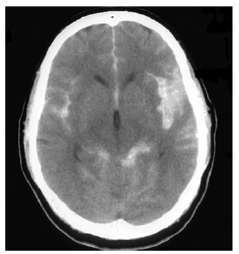

Uma paciente de 34 anos de idade procurou o serviço de emergência com quadro de cefaleia de forte intensidade, associado à rigidez de nuca e a vômitos há uma hora.

Realizou a tomografia de crânio mostrada a seguir.

Com base nesse caso hipotético, assinale a alternativa correta.